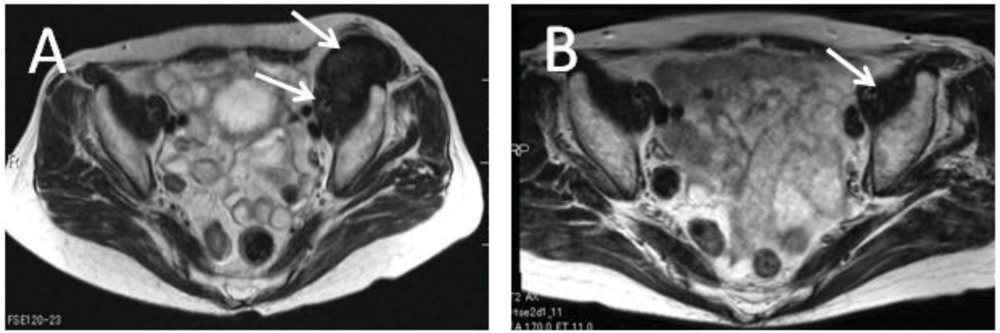

3. Conservative Therapy with Meloxicam (Since 2003)

- Nishida, Y.; Tsukushi, S.; Shido, Y.; Wasa, J.; Ishiguro, N.; Yamada, Y. Successful treatment with meloxicam, a cyclooxygenase-2 inhibitor, of patients with extra-abdominal desmoid tumors: A pilot study. J. Clin. Oncol. 2010, 28, e107–e109. [Google Scholar] [CrossRef]